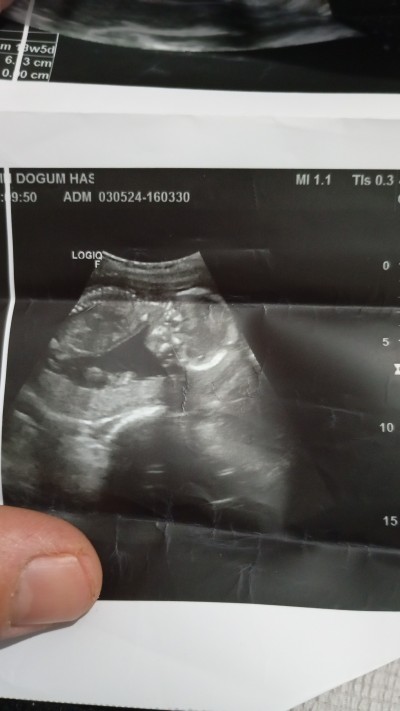

18 haftalık olduk ama cinsiyeti yine göremedim merka ediyorum 2 oğlum var çok şükür kız olsun çok istiyorum tabi Rabbim hayırlısını kolaylıkla nasıl etsin fark etmez tabiki tahmin alabilir miyim

Gebelik haftası 18 hafta

İlk öncelikle sağlıkla gelsin ama şuan görüntüde kafası var özel bölgesi görünmediği için tahmin yapamıyoruz zaten doktorda görse söylerdi eğer göstermiyorsa kız olabilir yüksek ihtimalle :)

Kemik yapısı kız gibi sağlıklan gelsin <3 doktor daha iyi bilir tabi

Bnde oğlana benzettim tabi gönlünden ne geçiyorsa Rabbim nasip etsin

Bu bebek erkek canim kafa yapisi değişik oluyor kizlarin

Benim oğlanın kafasına benziyo kızların kafasi farklı oluyor canim